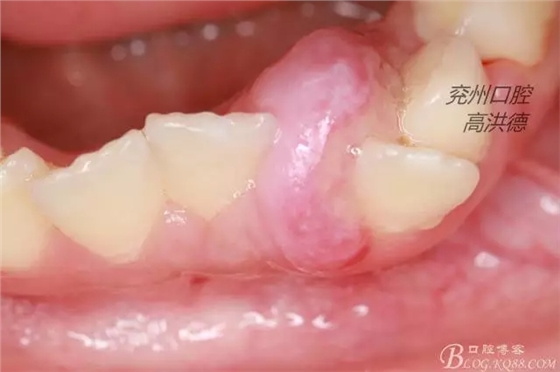

檢查見;患兒發(fā)育正常,神態(tài)自如,開口度正常,混合牙列,腫物位于31,32之間,32受腫物擠壓影響遠(yuǎn)中傾斜。

診斷:牙齦纖維瘤

牙齦纖維瘤以女性多見,青年和中年人多見,多發(fā)于牙齦乳頭部,常見于前磨牙區(qū),腫物較局限,呈圓形或橢圓形,有時呈分葉狀,大小不一,直徑有幾毫米至數(shù)厘米,有的有蒂有的無蒂,基底寬,隨著腫物生長可以破壞牙槽骨壁,牙可能松動、移位。本病例男性患者7歲,比較少見。